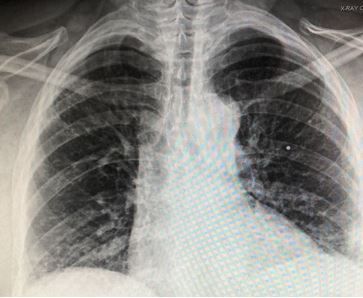

History of present illness: A woman in her mid-50’s with a history of rheumatoid arthritis presents to the hospital for 3 days of pleuritic left upper back pain without fever, shortness of breath, chest pain or cough. She also denies any injury and has not had this pain previously.

Vital signs & physical examination. Vital signs are normal except for a pulse oxygen level of 94% on room air. Physical exam is otherwise normal except for bilateral rales heard only with deep breathing.

Relevant test results

Laboratory studies: C-reative protein elevated at 25 mg/L; D-dimer elevated at 1600 mg/L FEU; CBC normal

Imaging: Chest x-ray, image below